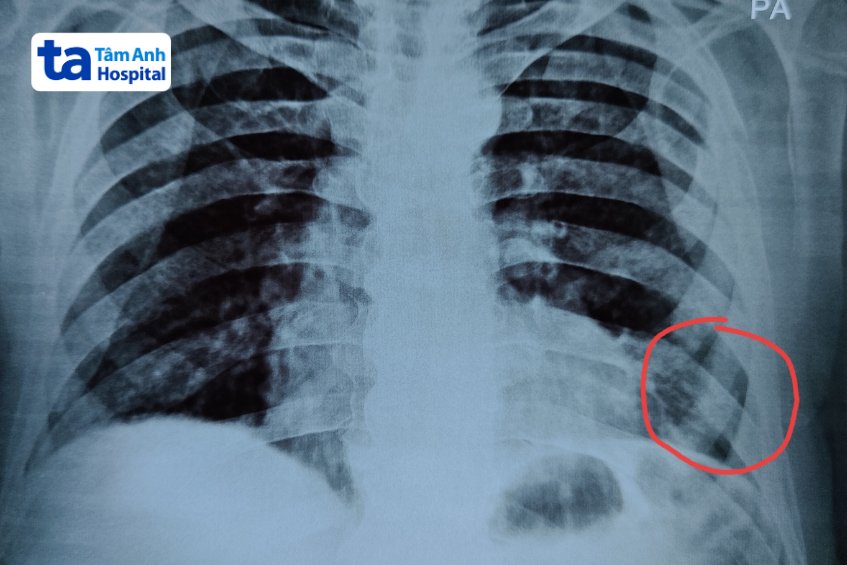

Chụp X quang xương sườn (chụp X quang để chẩn đoán, đánh giá tình trạng xương sườn và các vùng lân cận) là kỹ thuật chẩn đoán hình ảnh không xâm lấn, không gây đau, giúp tạo nên hình ảnh các cấu trúc của xương sườn một cách chi tiết, rõ nét bằng cách sử dụng tia bức xạ X chiếu qua vùng ngực. Thông qua ảnh phim X quang, bác sĩ có thể quan sát, đánh giá tình trạng xương sườn, vị trí và mức độ tổn thương nếu có. Từ đó đưa ra chẩn đoán và điều trị phù hợp.

Thông thường, bác sĩ sẽ chỉ định chụp X quang khi người bệnh gặp phải các tình trạng nghi ngờ có tổn thương vùng ngực, xương sườn hoặc xuất hiện các triệu chứng như sưng, đau tức ngực, khó thở, ho dai dẳng, đau khi ho…. Ngoài ra, kỹ thuật này có thể được bác sĩ chỉ định với mục đích theo dõi quá trình tiến triển của một số bệnh lý, từ đó đánh giá hiệu quả của phác đồ điều trị để có sự điều chỉnh kịp thời.

Chụp X quang xương sườn có quy trình thực hiện đơn giản, nhanh chóng, thường được bác sĩ chỉ định để đánh giá, chẩn đoán các tình trạng, bệnh lý như: